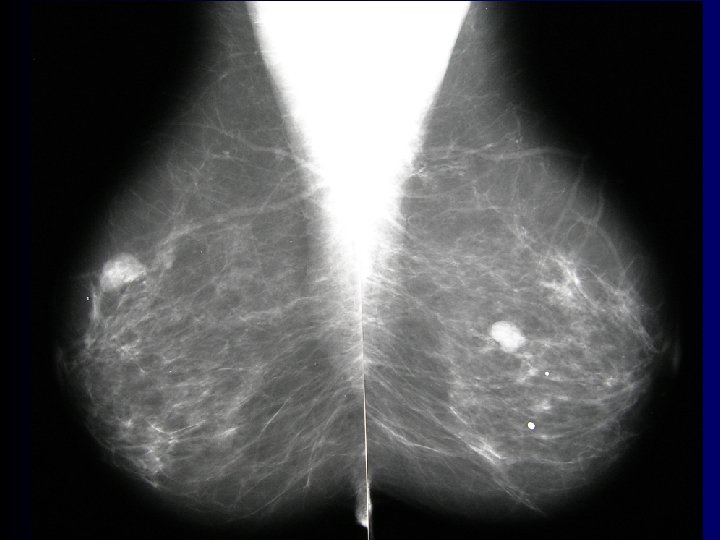

Carcinoma of breast • most frequent tumor in females Afflicts 9% of female population • clinical signs – bulging, skin/areolar invagination, ulceration • examination – palpation, ultrasound, mammography, lymph nodes • exstirpation Pictures – 1. LF UK

Mammary gland – lymph drainage 4 quadrants • nodi l. axillares – Sorgius‘ node = first (most caudal) one from group of nodi l. pectorales – on 2 nd/3 rd tooth of m. serratus anterior • nodi l. parasternales nodi. mediastinales ant. nodi epigastrci sup. + inf. • nodi l. supraclaviculares • contralaterally into other gland axilla plexus subareolaris Sappeyi

Adipose mamma Coopers ligaments

Average glandular mamma